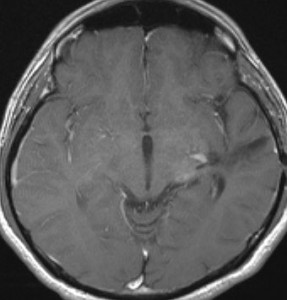

7才の時に音読でつかえるようになり,眼で何かを追っているような欠伸発作(左側頭葉てんかん)を繰り返すようになり,強直間代発作を生じて腫瘍が発見されました。下側頭回底面の皮質に発生した境界明瞭な腫瘍であり,周囲に脳浮腫を伴っています。T2強調画像で線維成分の多い硬い部分は低信号に,軟らかい部分はやや高信号となり,ガドリニウムでheterogenousに増強されます。グレード1の神経節膠腫としては非典型的な画像所見で術前診断は難しいもので,PXA pleomorphic xanthoastrocytoma も疑いました。もちろん治療としては開頭手術での全摘出です。術後に発作は消失しています。

構成要素はGFAP陽性の膠細胞が多く認められます。神経細胞様形態の細胞 ganglion cellではNeuN(+), CGA (+) synaptophisin (++), neurofilament (+)です。大型で腫大した核を有して核内封入体構造を有する好酸性もしくは淡明な細胞質を有する細胞が増殖してPXAを考えさせる部分像もありました。granular bodyも認められて,右の写真のように膠原線維の増生が目立つ部分もあります。これは表面の非常に硬い線維性の腫瘍部分です。MIB-1 indexは4%とやや高い値です。BRAF v600Eの変異が認められました。